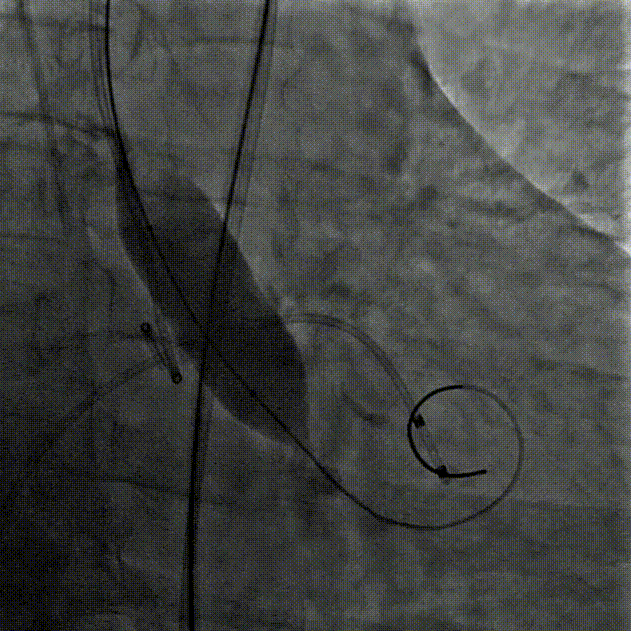

超声检测存在瓣中漏,瓣膜形态不佳,于是用22mm球囊后扩,最终造影显示瓣膜位置合适,冠脉灌注良好,左右钙化嵴处微量瓣周漏。

球囊后扩

术后根部造影

手术即刻超声评估,主动脉瓣工作良好,轻微瓣周漏。

超声评估